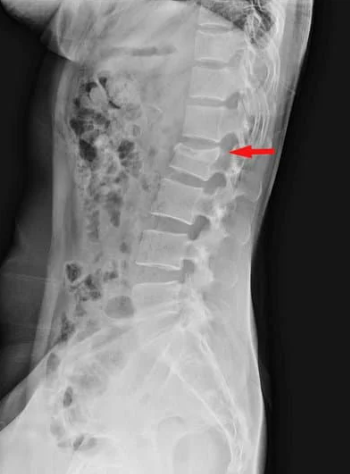

次に腰痛のレッドフラッグ(赤信号)の確認をします。レッドフラッグとは、見逃しては行けない腰痛疾患の総称で、代表的なものはがんの骨転移による転移性脊椎腫瘍や背骨の感染で生じる化膿性脊椎炎、高齢者によく生じる腰椎圧迫骨折などがあります。これらの疾患は放置すると腰痛で動けなくなるだけでなく、腰の神経を圧迫し、足のしびれや麻痺を生じます。神経圧迫の症状が進行すると手術を受けても後遺症が残るような状態(手遅れの状態)となり、その結果ADLが悪化し、致命的になる可能性もある怖い病気です。そのため、腰痛や神経症状が強い場合はレントゲンだけでなくCT・MRIもチェックし、これらのレッドフラグを見逃さないように丁寧な診療を心がけています。

腰椎圧迫骨折

腰椎圧迫骨折は骨粗しょう症を背景にして、転倒などをきっかけに生じる高齢の方に多い病気です。いつの間にか骨折と言われ、転倒などのきっかけがない場合もあります。腰の痛みはかなり強く、動けなくなり入院となることもありますので、まずは腰椎圧迫骨折にならないように予防(骨粗しょう症の治療)を行うことが重要になってきます。

腰椎圧迫骨折の診断

診断はレントゲンで行います。正面と側面を確認し、つぶれている腰骨がないかチェックします。腰骨がつぶれてなくても安心はできず、不顕性骨折と言ってレントゲンでわからない骨折もあるので、痛みが強い場合はMRIで診断することもあります。